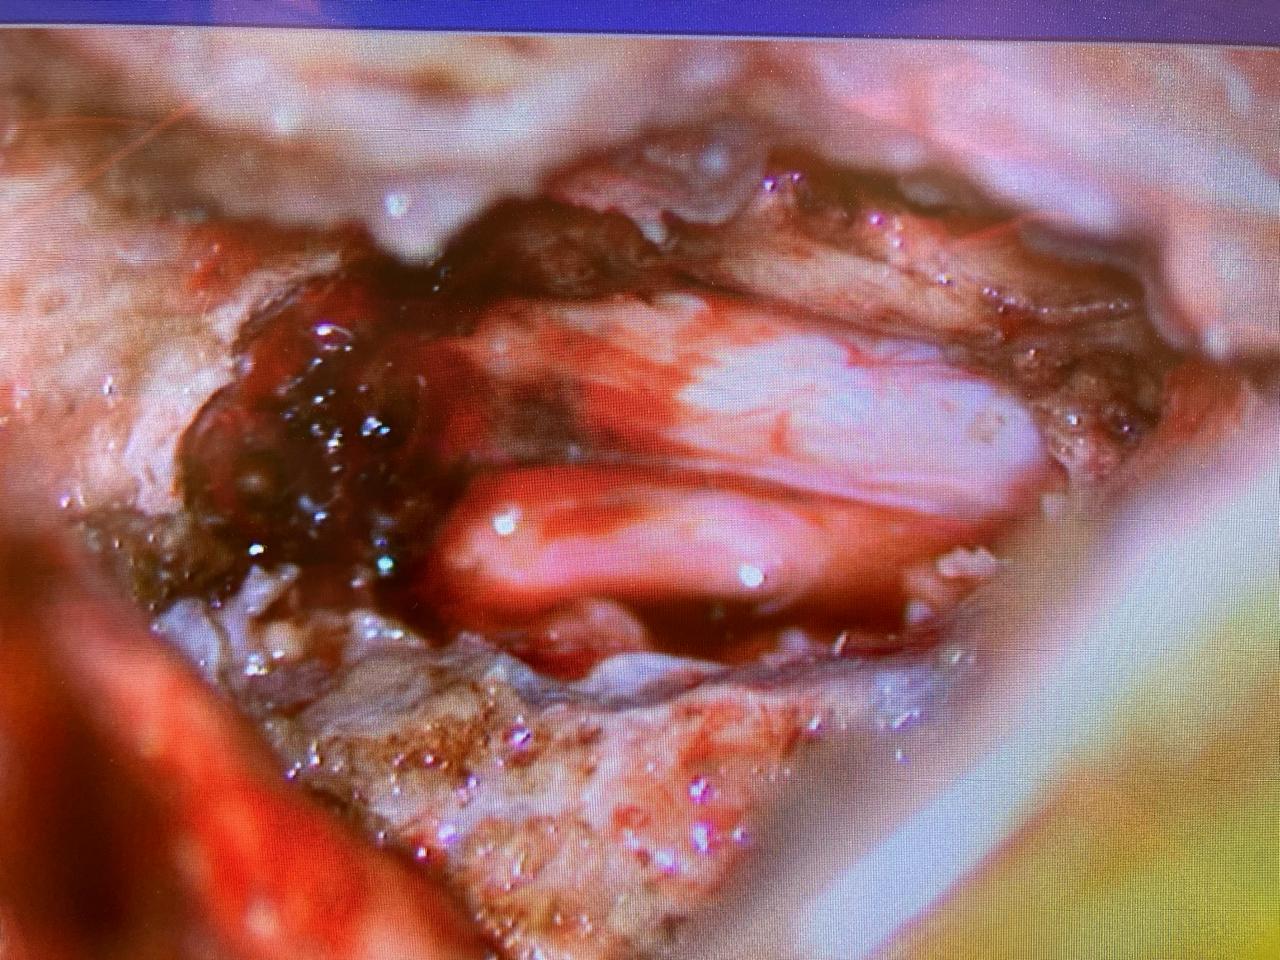

Dr. Vahagn Tosunyan Neurosurgery & Spine

Gallery